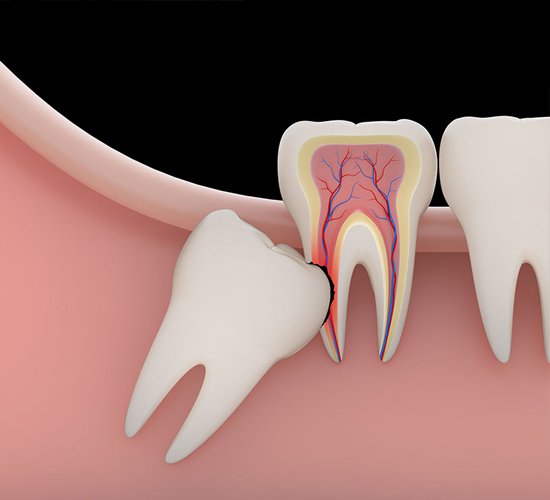

Tooth Extraction

( Wisdom Tooth )

Careful removal of impacted wisdom teeth with patient comfort in mind.